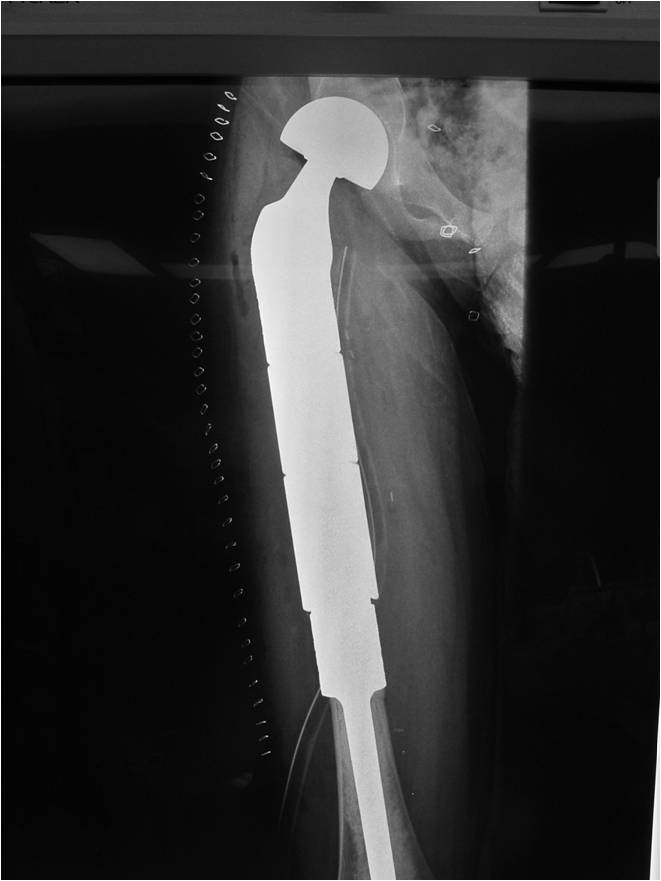

- Femur: Single most common site

- Most protocols administer preoperative chemotherapy then surgery is performed. Surgery is followed by several courses of postoperative chemotherapy.

- Ewing sarcoma responds well to chemotherapy. Often there is a dramatic reduction in size of the tumor.

- Surgical resection

- Limb sparing surgery whenever feasible unless there will be a large leg length discrepancy that can not be accomodated for with surgery

- Rarely ever an amputation since Ewing sarcoma are sensitive to radiation

If surgical resection is not feasible, radiation may be utilized for local control (instead of an amputation) since Ewing sarcoma is highly sensitive to radiation, at least as per the author’s opinion. There may be some tumors that are selectively treated with radiation instead of surgery however most patients as of 2008 are treated with limb sparing surgery whenever feasible. Sometimes radiation is used in conjunction with surgery if a wide margin was not obtained at the time of surgery. The decision to administer radiation depends on size of tumor, site of tumor, response of tumor to preoperative chemotherapy and risks vs benefits of radiation.